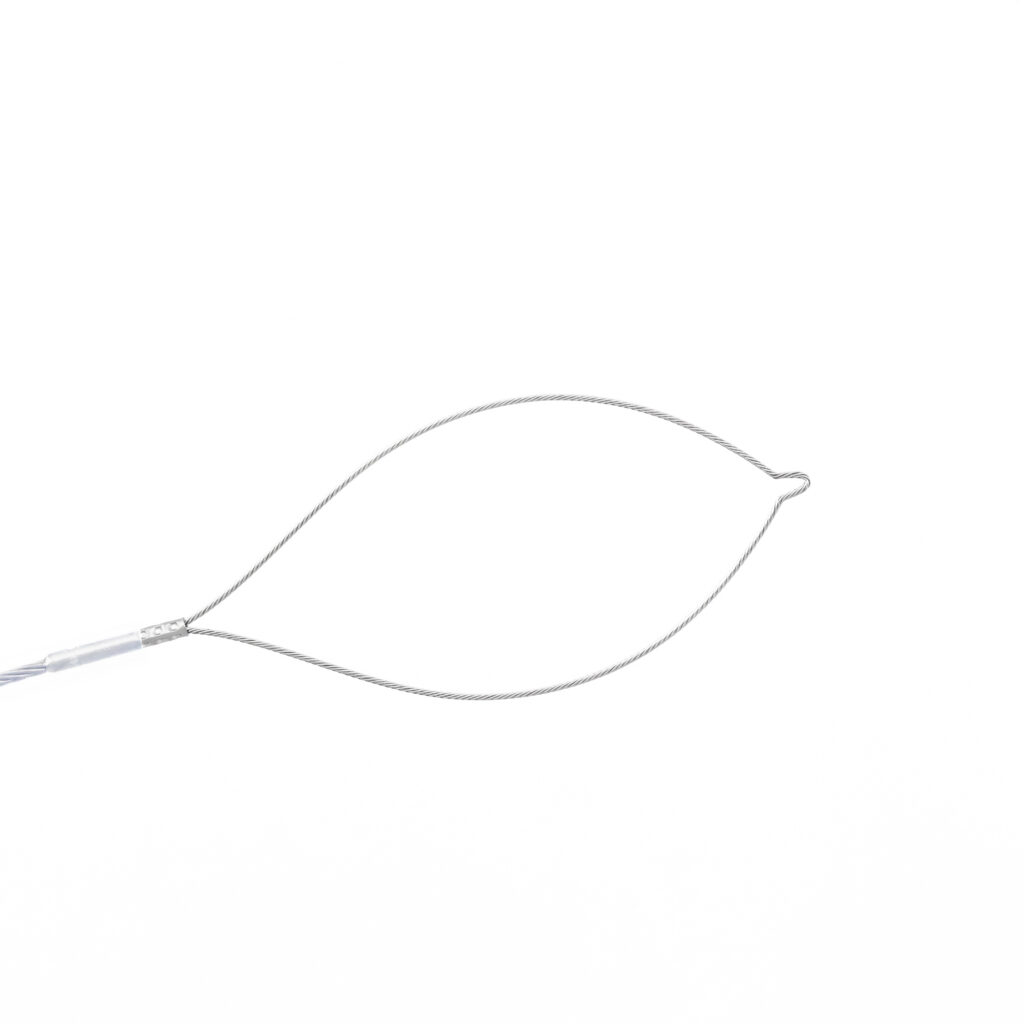

To make the removal of polyps in everyday routine as efficient as possible, Micro-Tech has developed a range of disposable polypectomy snares which perfectly combine quality with cost effectiveness. Each oval snare is made of a specially stranded wire, with enduring radial force, high dimensional stability, and precise cutting properties. The 3-ring handle offers a secure hold and transmits every movement reliably to the snare.

- High strength of shape